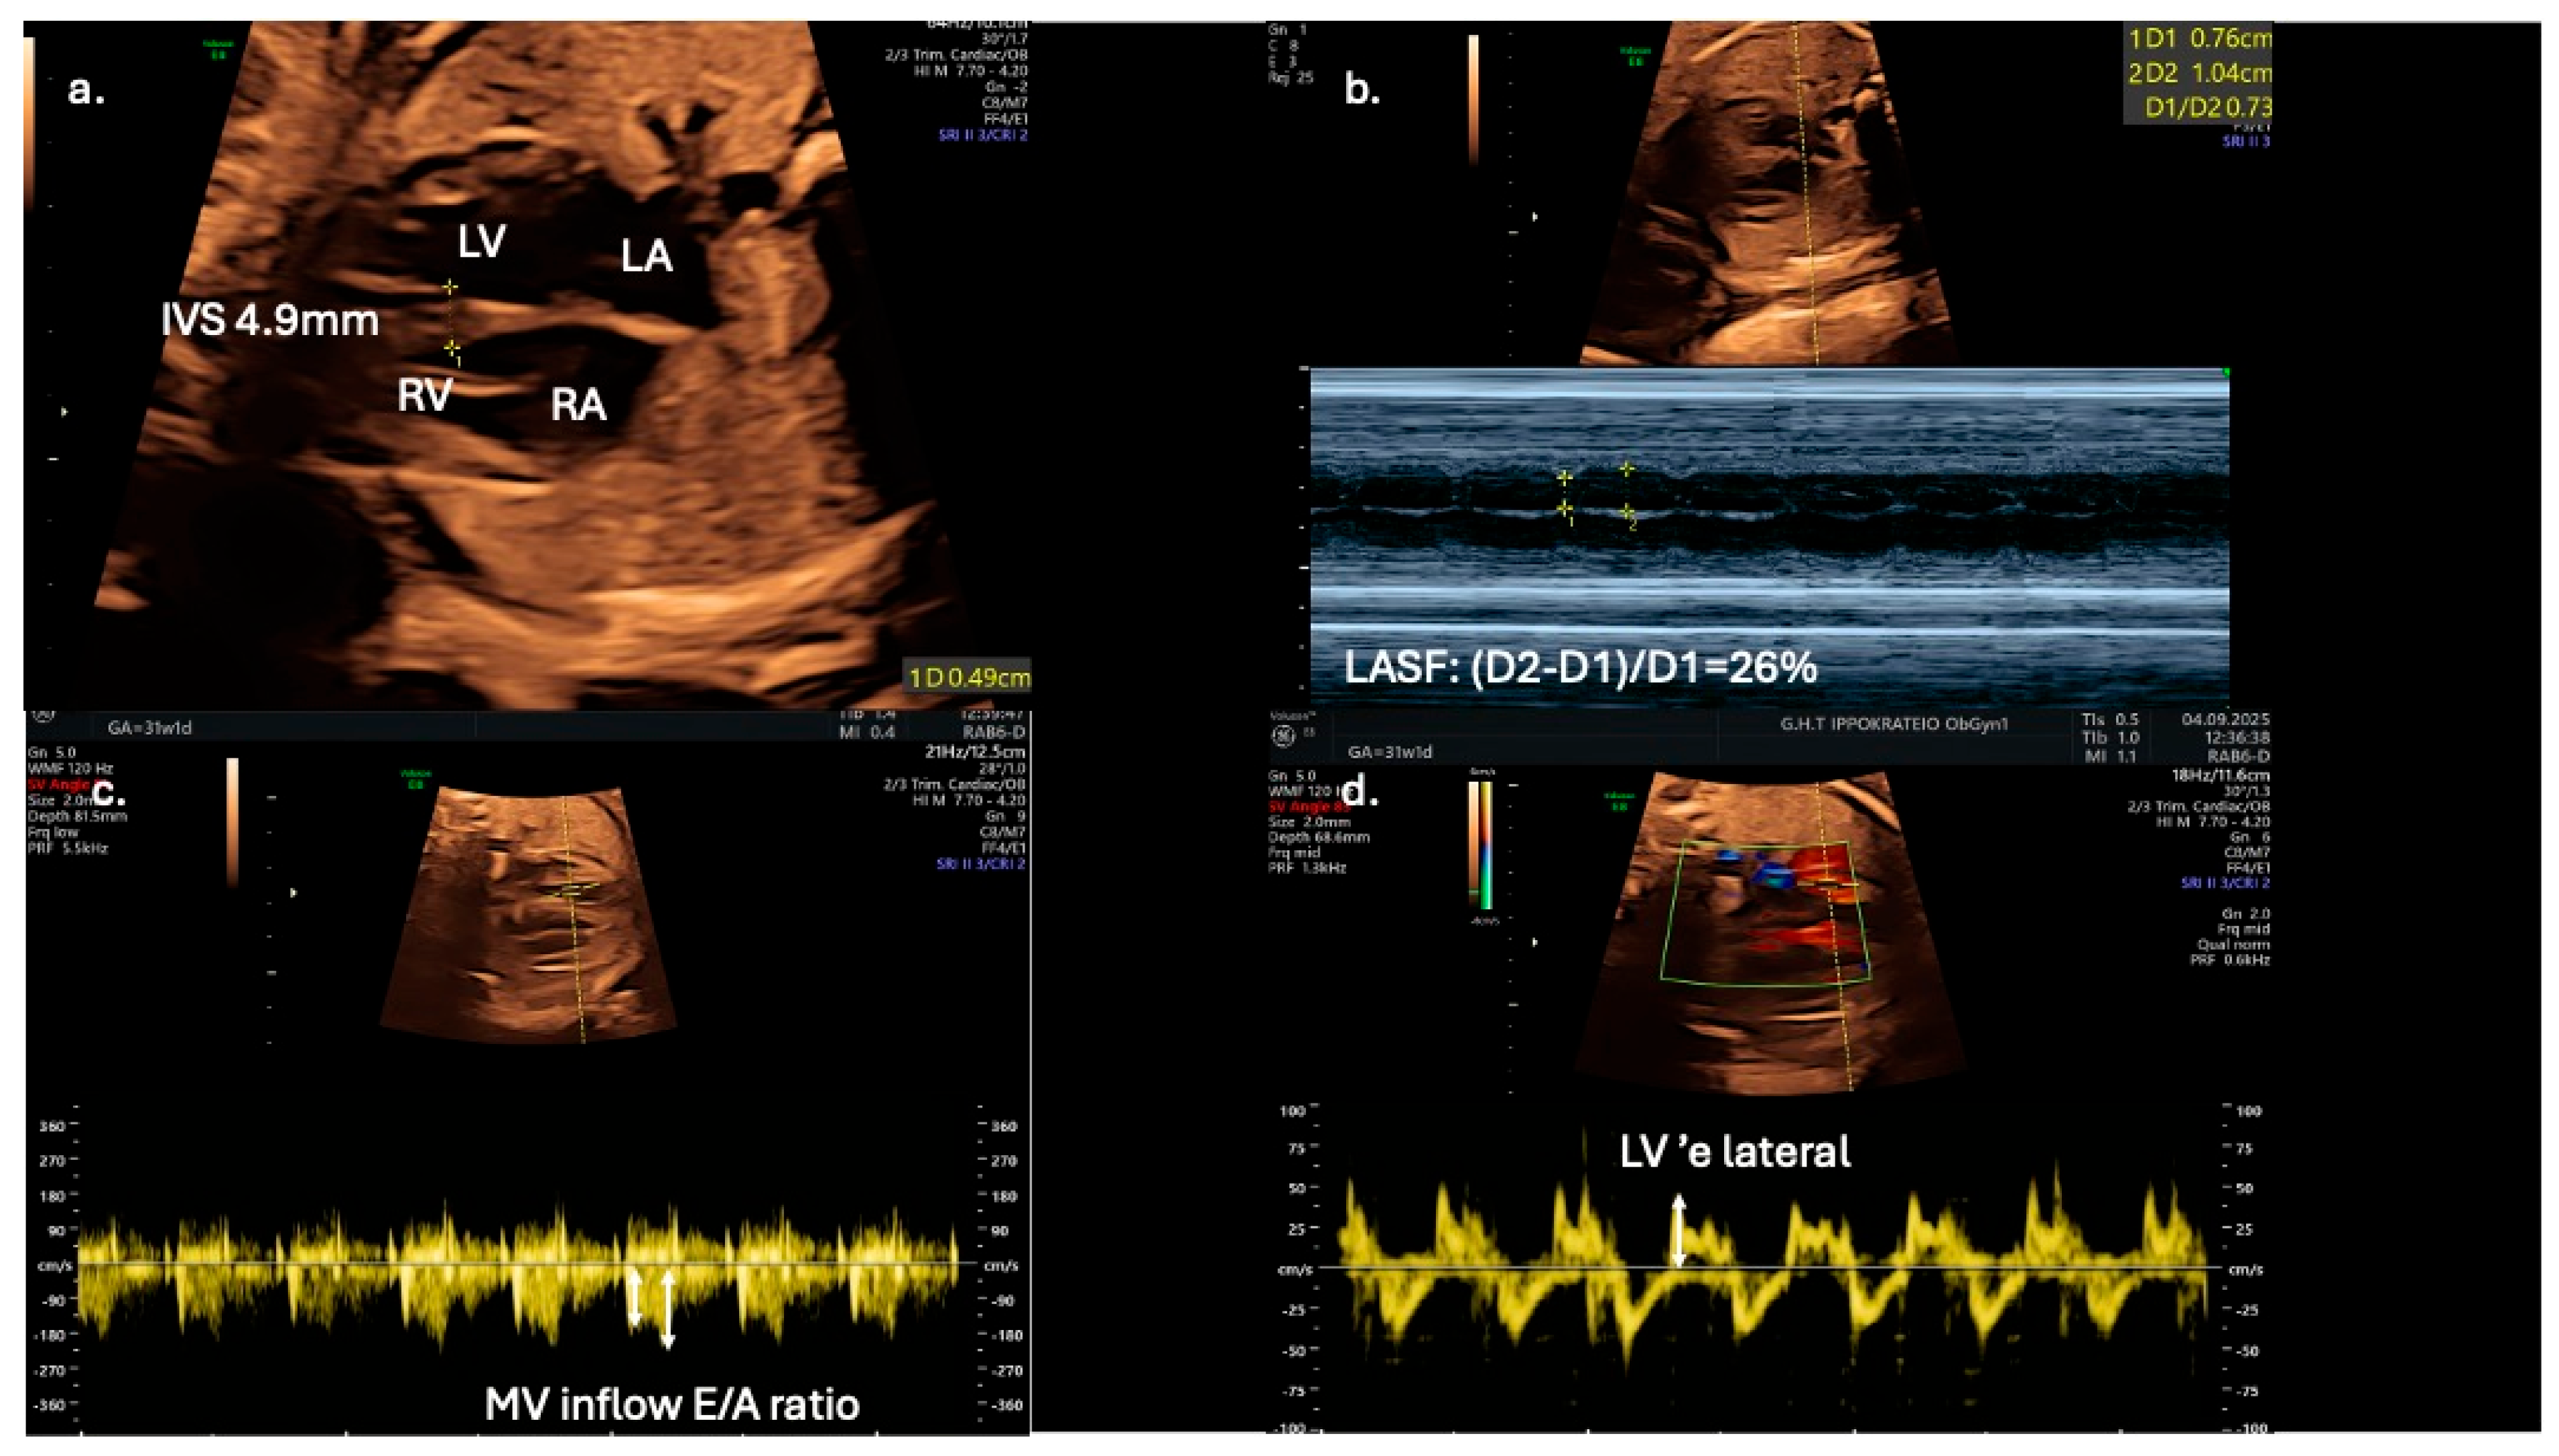

| Mohsin M. et al., 2019 [14] | The purpose of this study was to assess fetal cardiac function in normal fetuses (control group) compared to those who are exposed to gestational diabetes mellitus using different echocardiographic measurements, and to explore the application of left atrial shortening fractioning determination of fetal diastolic function with gestational diabetes mellitus. | 50 women with gestational diabetes and 50 women with a healthy pregnancy were included in the study. | Fetal echocardiography was performed and structural as well as functional fetal cardiac parameters were measured. | Fetuses of gestational diabetic mothers have altered cardiac function even in the absence of septal hypertrophy, and left atrial shortening fraction can be used as a reliable alternate parameter in the assessment of fetal diastolic function. |